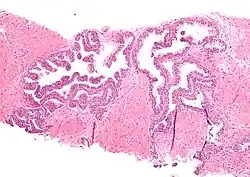

Micrograph showing high-grade prostatic intraepithelial neoplasia. H&E stain.

Histopathology of high-grade prostatic intraepithelial neoplasia (HGPIN) with typical features, H&E stain.[6]

High-grade prostatic intraepithelial neoplasia.

HGPIN typically has one of four different histologic patterns:[2]

Microscopically, PIN is a collection of irregular, atypical epithelial cells. The architecture of the glands and ducts remains normal. The epithelial cells proliferate and crowding results in a pseudo-multilayer appearance. They remain fully contained within a prostate acinus (the berry-shaped termination of a gland, where the secretion is produced) or duct. The latter can be demonstrated with special staining techniques (immunohistochemistry for cytokeratins) to identify the basal cells forming the supporting layer of the acinus. In prostate cancer, the abnormal cells spread beyond the boundaries of the acinus and form clusters without basal cells. In HGPIN, the basal cell layer is disrupted but present. PIN is primarily found in the peripheral zone of the prostate (75-80%), rarely in the transition zone (10-15%) and very rarely in the central zone (5%), a distribution that parallels the zonal distribution for prostate carcinoma.[7]

Several architectural variants of PIN have been described, and many cases have multiple patterns. The main ones are tufting, micropapillary, cribriform, and flat. Although these different appearances may cause confusion with other conditions, they have not been found to be of clinical importance. Rarer types are signet-ring-cell, small-cell-neuroendocrine, mucinous, foamy, inverted, and with squamous differentiation.[3]